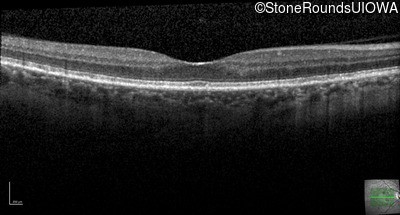

Late Onset Retinal Dystrophy (IIIA3)

Age at visit: 61 years

This 61 year old woman reports some moderate night blindness over the past 10 years.

Diagnosis & molecular findings

Late Onset Retinal Dystrophy C1QTNF5 Ser163Arg AGC>AGA   AD